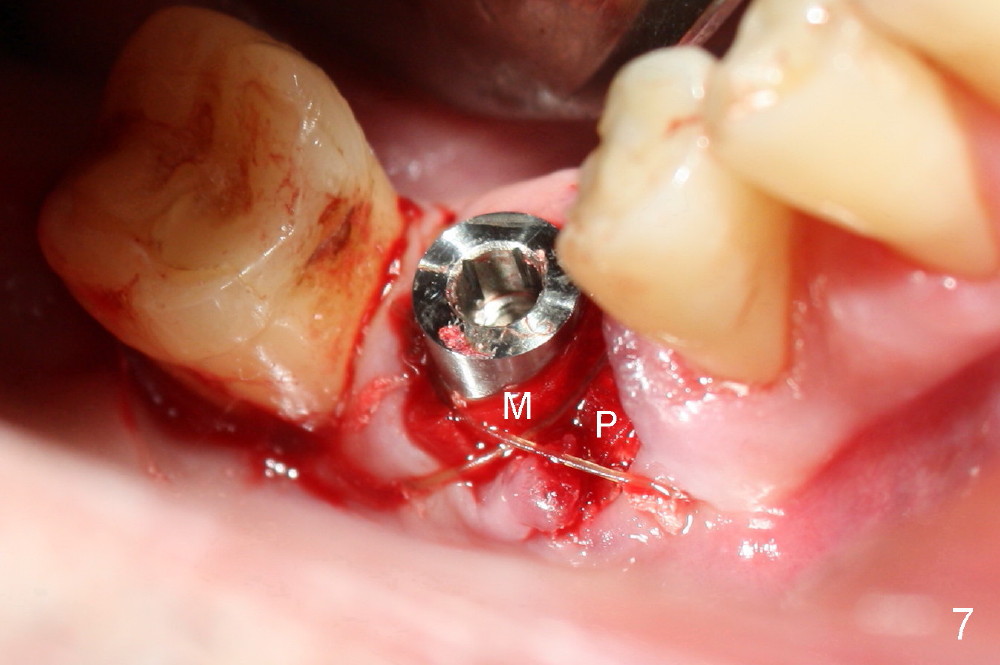

As to where to place an implant, we try to engage the largest tap (8 mm in diameter) into the mesial socket without binding. The buccal plate of the mesial socket is missing.  It is risky to extend osteotomy in the mesial socket.  Besides, the septum (Fig. 4 S) is not as tall as the distal socket (D).  It appears that the distal socket is the safest place to place an implant.  Furthermore, no drill is used for distal osteotomy.  Instead two osteotomes (3.5x15 and 4x15 mm tapered osteotomes) are used to expand the distal socket with intention to push the septum mesially.  Since the bone density is high, the osteotomes seem not to work as effectively as expected.  Then a 4.5x17 mm tap is placed at the depth ~ 14 mm with stability (Fig.5).  Finally a 5x14 mm tissue-level implant is placed with insertion torque >60 Ncm (Fig.6).  Allograft is placed in the mesial socket and buccal aspect of the distal socket, followed by insertion of collagen plug and membrane (Fig.7).  After insertion of an abutment (Fig.8 (taken 6 days postop) *), perio dressing (P) is applied to cover the wound.  There is no postop paresthesia.